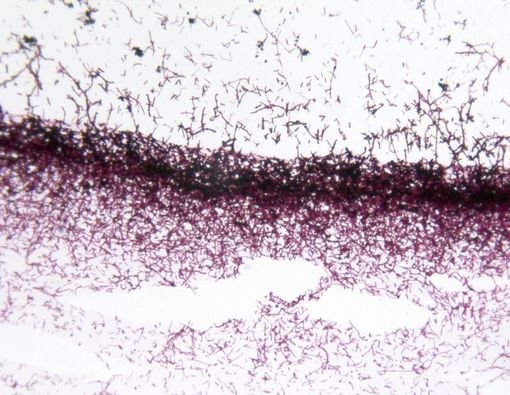

Infeksi jamur candida merupakan musuh bagi banyak orang. Infeksi jamur ini disebabkan oleh jamur candida, utamanya Candida albicans.

Mikroskopis ini sering ditemukan di sekitar kulit, mulut, atau usus. Jika tidak ditangani secara tepat, jamur candida dapat menyebar ke bagian lainnya, misalnya jantung, usus, ginjal, bahkan otak.

Diet anti-candida lainnya adalah dengan mengonsumsi kunyit. Menurut penelitian, jamur candida dapat dibunuh atau dihambat pertumbuhannya dengan kurkumin, komponen aktif utama dalam kunyit.

Studi lain menunjukkan, kurkumin dapat mengurangi kemampuan jamur untuk menempel pada sel di mulut orang dengan HIV. Bahkan, kurkumin disebut-sebut lebih efektif daripada obat antijamur yang bernama flukonazol.

Namun demikian, penelitian ini masih terbatas pada tabung reaksi. Belum jelas apakah suplemen kurkumin akan berefek sekuat itu pada manusia.